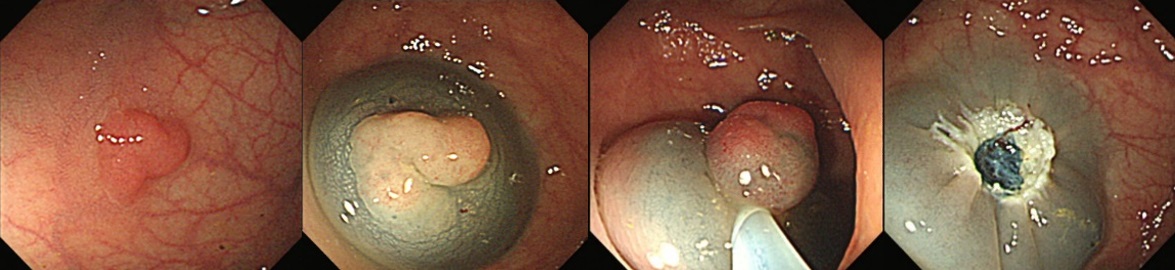

大腸ポリープ切除術、早期癌に対する内視鏡的粘膜剥離術、胃潰瘍などからの出血に対する内視鏡的止血術、食道静脈瘤からの出血に対する結紮術、アニサキス(寄生虫)や薬パッケージの誤飲に対する異物摘出術など。また胆道・膵臓系では、内視鏡を用いた胆石除去や、胆道感染や癌に伴う黄疸に対する内視鏡的な減黄術(ステント留置術)など各種行っております。

『大腸ポリープ切除術(EMR)』

『早期胃癌に対する内視鏡的粘膜下層剥離術(ESD)』